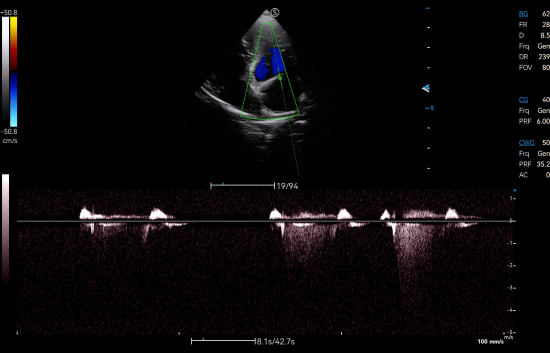

CW Mode sensitively detects high-velocity blood flow signals to identify cardiac abnormalities such as mitral regurgitation, which is commonly observed in dogs with degenerative mitral valve disease